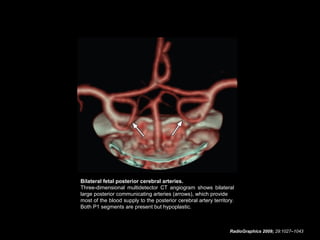

Fetal Origin of the Posterior

Cerebral Artery

• In the presence of this anomaly, the caliber of the

posterior communicating artery may be the same as or

greater than that of the ipsilateral P1 segment, and the

dominant blood supply to the occipital lobes comes from

the internal carotid artery.

• Fetal origin of the posterior cerebral artery occurs when

the embryonic posterior cerebral artery fails to regress.

• It may occur on the right side (10% of the general

population), the left side (10% of the general population),

or bilaterally (8% of the general population).

• The P1 segment may be absent in fetal origin of the

posterior cerebral artery, but its absence is an

uncommon finding.

RadioGraphics 2009; 29:1027–1043

Bilateral fetal posterior cerebral arteries.

Three-dimensional multidetector CT angiogram shows bilateral

large posterior communicating arteries (arrows), which provide

most of the blood supply to the posterior cerebral artery territory.

Both P1 segments are present but hypoplastic.